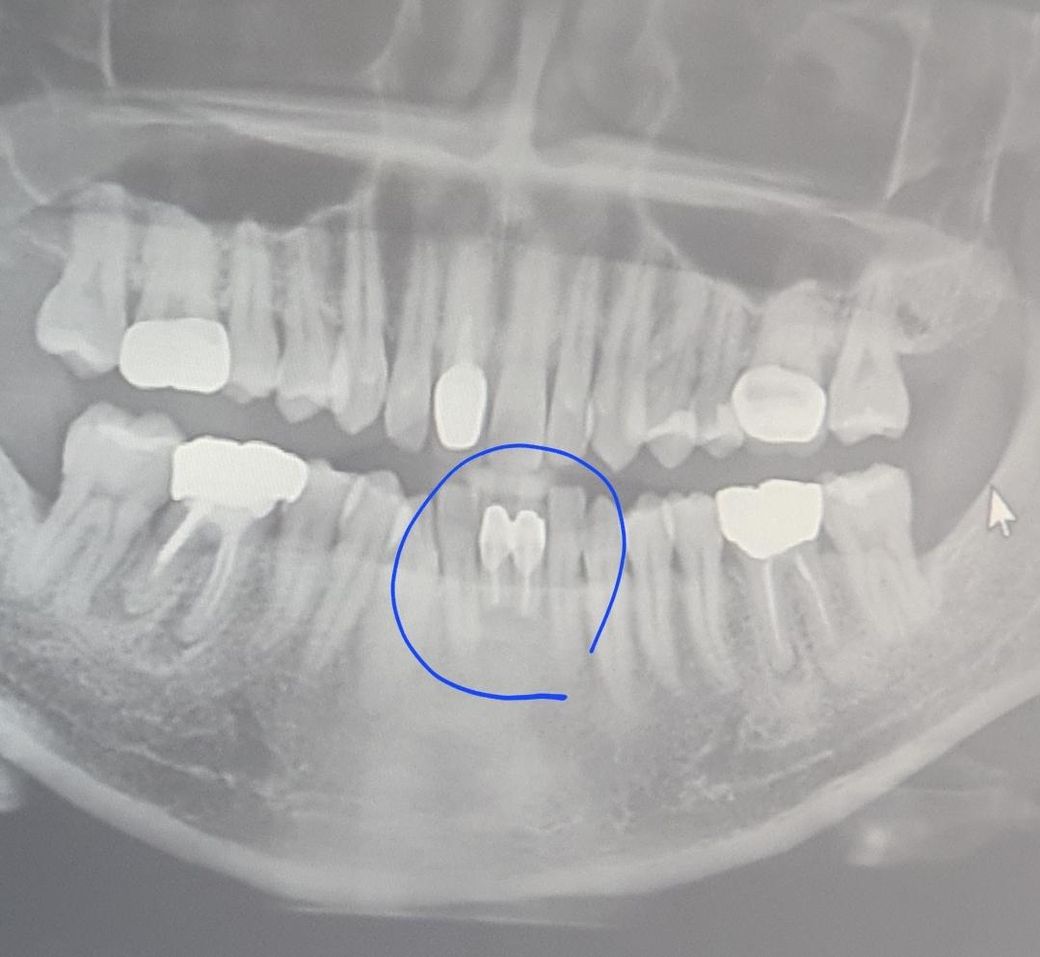

앞니 임플란트 수술시 가능여부 알려주세요

앞니 치근단절제술을 했었고

현재 크라운고철부분이 까맣게보여 새로 씌울지

그냥쓰다 임플란트를 해야 할지 생각중인데

임플란트시 공간이 부족해서 나사 1개밖에 못박을수 있다는데

1개면 너무 약해서 제가 생각하기엔 불안해보이는데

여기에 2개가 불가능할까요?

아래 앞니의 경우에는 치아 크기 자체가 작아서 2개를 뽑고 하나 심고 하나는 가짜 치아를 일반적으로 하게됩니다.

임플란트를 하기 위해서는 임플란트와 인접지아 그리고 임플란트 간의 일정한 간격을 두어야 합니다. 공간이 너무 좁을 시에는 임플란트가 들어갈 공간이 적을 수 있습니다. 하지만 그만큼 얇은 임플란트를 사용한다면 가능할 수도 있습니다. 자세한 확인을 위해서는 치과에서 진료를 받아보는 것이 좋습니다.

두개를 식립하기엔 공간이 부족하여 한개를 심어야할 가능성이 높아보입니다. 파노라마로는 정확한 진단은 한계가 있습니다.

공간이 아주 좁긴 합니다. 2개를 심고자 한다면 아주 얇은 전치부용 임플란트를 사용해야 하고 수술 실패나 파절의 위험도 있습니다. 1개를 심었을때와 2개를 심었을때 장단점이 있을 것 같습니다.